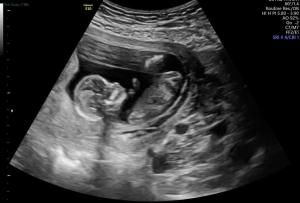

If you came here for the ultrasound pics, I promise I won’t disappoint! We’ve had a few ultrasounds already, so here are our favorite images from our 8 week, 10 week, and 12 week ultrasounds.

Once we have our 20 week ultrasound, we’ll know the gender – and we promise to share it with you – and to share how we tell Little Man and our families! Stay tuned!